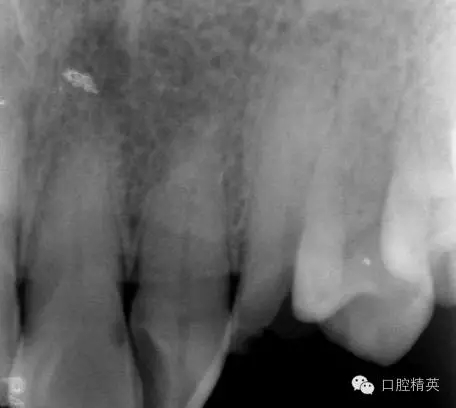

口內(nèi)檢查: 23殘根,位于齦上3MM,根管口探無反應(yīng),叩(+-),無松動(dòng),牙周無紅腫.X片示:23根管無阻射,根尖骨密度降低.

圖2 治療前X片: 23殘根,根尖區(qū)骨密度降低.